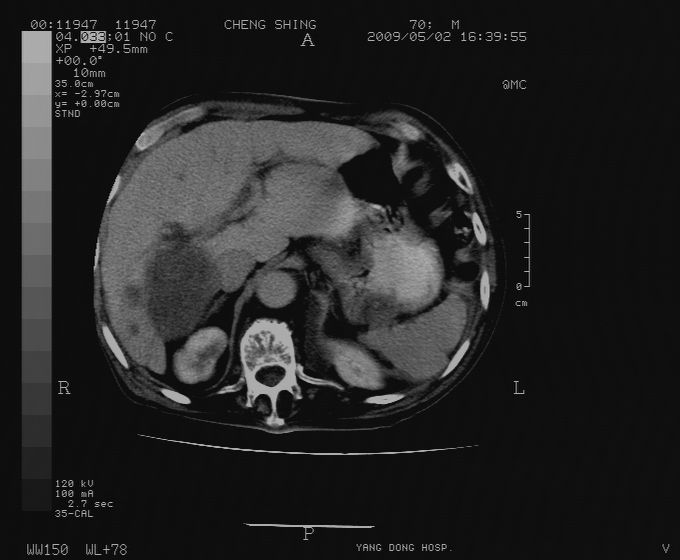

标题: CT19743:男70岁,肺部疾病入院,B超发现肝右叶占位,CT [打印本页]

标题: CT19743:男70岁,肺部疾病入院,B超发现肝右叶占位,CT

肝表面塌陷,病灶周围有子灶,前面较大子灶强化符合肝癌表现,考虑肝癌肝转移可能性大.

1.考虑肝癌肝转移

2.两侧胸水,左下肺不张!

1)考虑肝癌并肝内转移。2)少量腹水。3)双侧胸腔积液。

1)考虑肝癌并肝内转移。2)少量腹水及双侧胸腔积液。3)椎体退变。